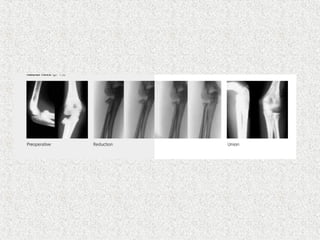

 2/3rd of medullaryisthmus nail size  Radius  Ascending technique  2cm proximal to distal epiphyseal plate  Superficial radial nerve

 Ulna  Descendingtechnique  2cm distal to apophyseal plate  Olecranon apophysis

 Tips pointtowards each other  Oval bracing of interosseous membrane